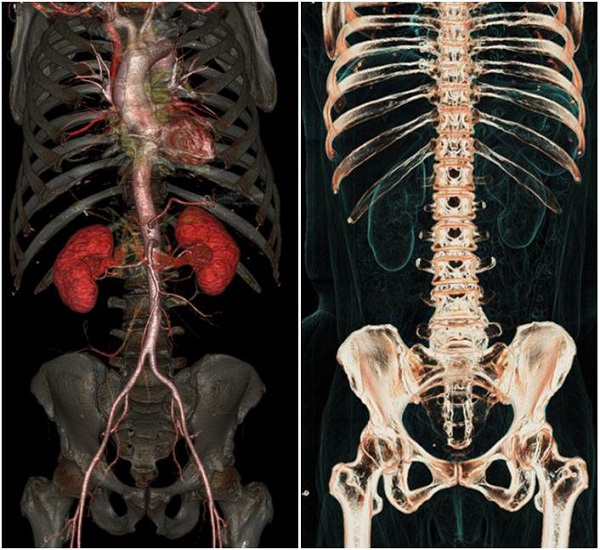

این روش توموگرافی رایانهای اشعه ایکس نیز نامیده میشود که اغلب در بیمارستان برای مشاهده تومورها، شکستگی استخوان و خونریزی داخلی استفاده میشود.

عروق، روده، قلب، مغز، استخوانها با جزئیات منحصربفردی به تصویر کشیده میشوند.

اسکنر GE برای بیمارانی که از ضربانساز قلبی یا ایمپلنتهای فلزی در داخل بدن استفاده میکنند، کاملا ایمن و بی خطر است.

محققان امیدوارند که با کمک اسکنر GE، اسکن پزشکی ارزانتر، سادهتر و دقیقتر را در اختیار بیماران و پزشکان قرار دهند.